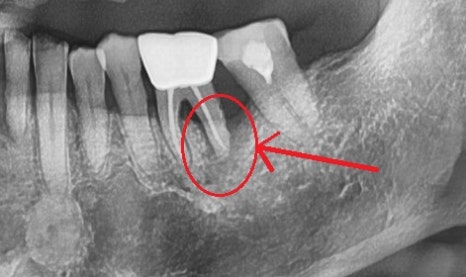

좌측 사진은 잇몸에 고름주머니가 생긴 증상이고,

이것은 뿌리 쪽 염증이 바깥 뼈를 녹이며 외부로

노출이 된 상태이며

이것을 확인하기 위해 고름주머니를 통해

염증의 근원지가 어디인지 엑스레이를 통해 알아보았습니다.